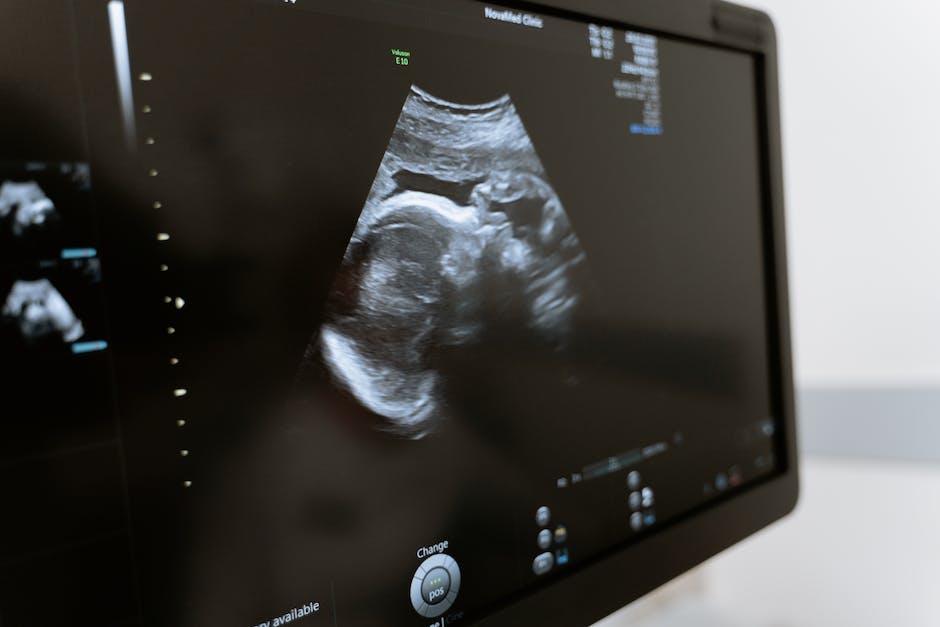

수원산부인과는 최신 시설과 장비를 갖추고 있는데, 이는 치료의 효과성과 효율성에 큰 영향을 미칩니다. 최신 시설과 장비를 사용하면 정확한 진단과 치료를 수행할 수 있으며, 환자들에게 불필요한 시간과 비용 소요를 줄여줍니다. 또한, 최신 시설과 장비는 안전성과 편의성을 제공하여 환자들에게 더 나은 치료 환경을 제공할 수 있습니다.